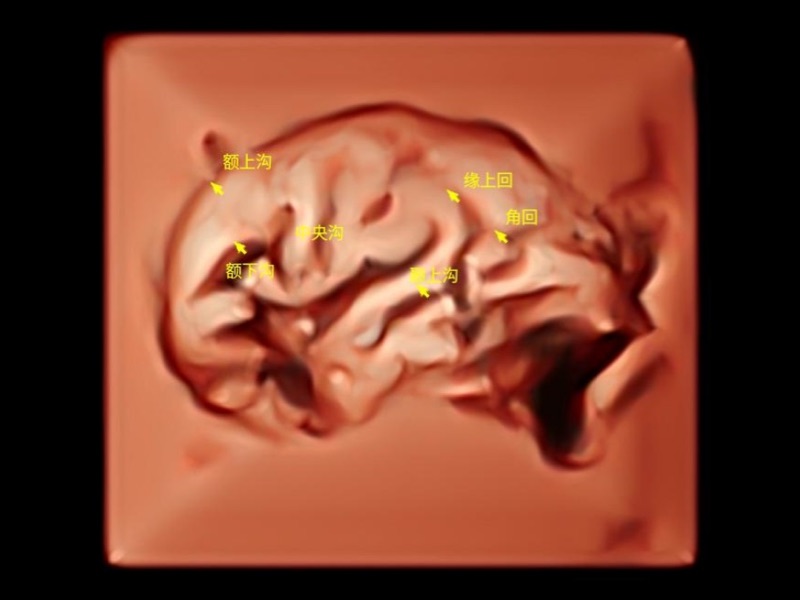

作为开立医疗全新打造的超高端旗舰超声产品,从探头抬起唤醒开启扫查到多维探头发射接收,通过先进的场成像发射、自适应聚合重建等技术,基于RF Data原始射频数据在图像生成、高端功能等方面实现突破,为妇产科、儿科提供全方位临床解决方案。

天工开物 智见苍穹

独有场成像发射技术

自适应聚合重建技术

独家XPUs混合硬件架构

构建多维智能生态